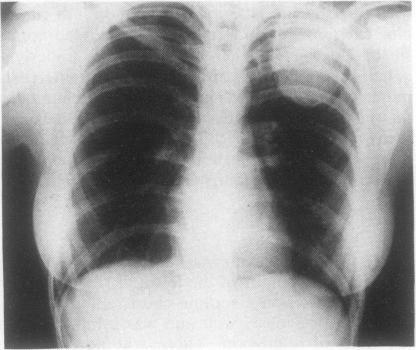

肋骨动脉瘤样骨囊肿

Aneurysmal bone cyst of the rib.

Aneurysmal bone cysts are uncommon lesions, especially in the ribs. Four patients with aneurysmal bone cysts of the rib are presented and previously reported cases reviewed. A brief discussion of the clinical manifestations, pathology, aetiology, and current treatment of aneurysmal bone cyst is also included.

动脉瘤样骨囊肿是一种罕见的病变,尤其是在肋骨部位。本文报告了4例肋骨动脉瘤样骨囊肿患者,并对既往报道的病例进行了回顾。文中还简要讨论了动脉瘤样骨囊肿的临床表现、病理、病因及当前的治疗方法。